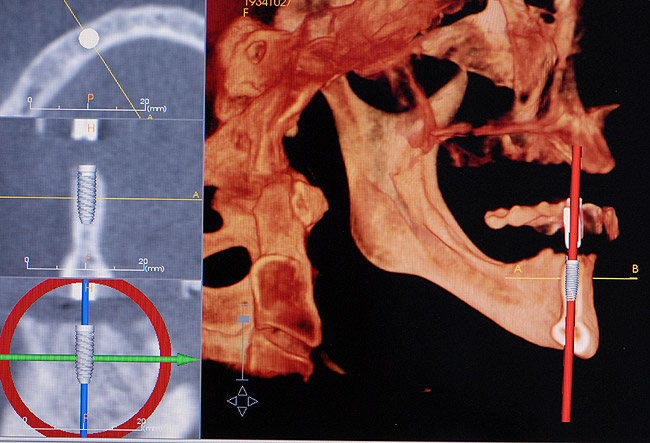

Patient expectations remain extremely critical. The treatment options must be able to meet these expectations, otherwise tooth replacement of the edentulous area with dental implants should not be attempted. A set of mounted casts in centric relation with a full contour diagnostic wax-up, including the hard- and soft-tissue deficits, is mandatory prior to initiating treatment. This is beneficial in accessing the edentulous space and communicating the information concerning the edentulous defect with the laboratory technician, the implant surgeon, and most importantly, the patient. In addition, CBCT can also be extremely helpful in diagnosing the edentulous site 3-dimensionally and providing vital information to the surgeon prior to implant placement (Figure 9). Only after the diagnosis and treatment plan is fully understood by all parties should the treatment be initiated. In many situations, hard- and soft-tissue grafts are necessary in order to reconstruct the edentulous site as near to its original contours as possible (Figure 10 through Figure 12). This will significantly enhance proper positioning of the implant for prosthetic needs and help to increase the prognosis for an esthetic result.27 At the time of implant placement, a surgical template should be used to help ensure that the implant is placed in the proper position. The surgical template can be fabricated from the diagnostic wax-up or generated from planning software using the Digital Imaging and Communications in Medicine data obtained from the CBCT. The esthetic result is generally dictated at the time the implant is placed, hence the need for such a detailed assessment.

Figure 9  A computed tomography scan can provide additional information to aid the implant team for proper placement of the implant(s).

Figure 9